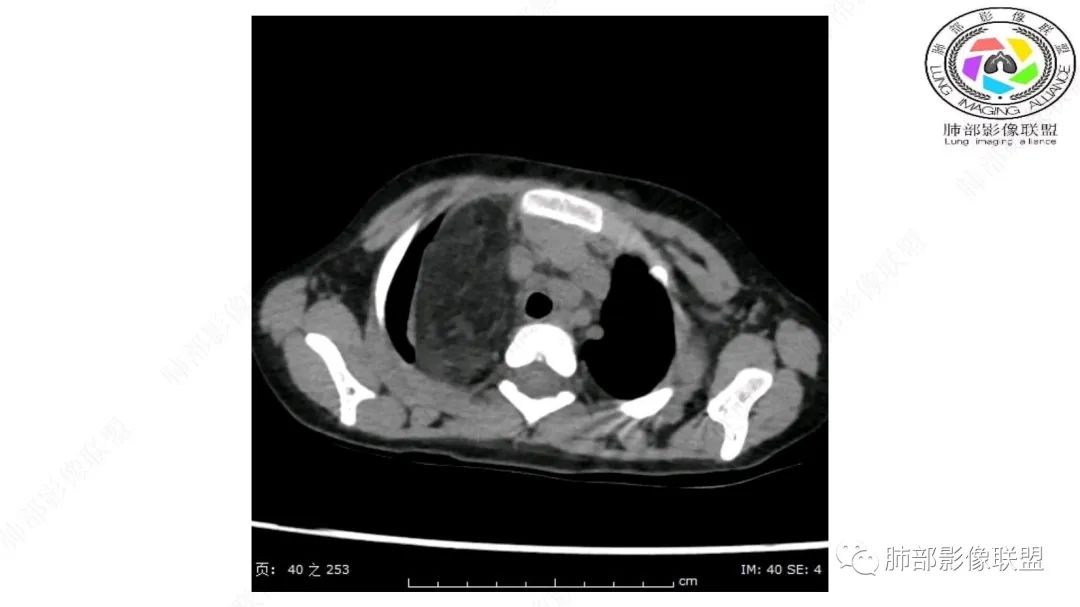

右上纵隔混杂密度肿块,边缘光整,与纵隔分界清,其内多发脂肪密度,增强无明显强化,其内血管穿行,考虑纵隔脂肪母细胞瘤,鉴别畸胎瘤,脂肪肉瘤。

右纵隔团状,密度不均,脂肪密度为主,内可见腺体样组织,类似乳腺,病灶边缘有分叶,与胸腺关系密切,增强后血管穿行。考虑胸腺脂肪瘤(不典型垂乳征),鉴别畸胎瘤。

3岁儿童,右纵隔占位,内部间多发脂质成分及斑片状稍高密度影,考虑纤维成分,增强似有强化。病灶内血管未见明显侵犯,可考虑脂肪母细胞瘤,冬眠瘤等。

三岁小儿,右侧纵隔巨大脂肪密度肿块,肺动脉穿行其中,密度欠均匀,未见明确实性成分,纵隔脂肪母细胞瘤,冬眠瘤鉴别纵隔脂肪增多症(多弥漫对称)。

患儿3岁 咳嗽检查发现纵隔占位。右肺上叶受压表现,占位以脂肪组织密度为主,似见分隔,首先考虑为脂肪母细胞瘤,鉴别脂肪瘤,畸胎瘤。

幼儿,右上纵隔团块状脂肪密度影,边缘清晰,内可见血管及支气管穿行,考虑脂肪瘤,鉴别畸胎瘤。

幼儿,右上纵膈团块,脂肪密度,内见分隔,增强病灶内见血管穿行,结合患者年龄,考虑脂肪母细胞瘤,鉴别脂肪瘤。

纵隔畸胎瘤,右前上纵隔团状脂肪密度?粘液样密度为主病变,病灶软边缘有分叶,内可见分隔,增强后血管穿行。3岁。考虑纵隔脂肪母细胞瘤,鉴别畸胎瘤。

定位肺外纵隔内,脂肪密度,内可见纤维分割,3岁,脂肪母,鉴别畸胎瘤。

右上纵膈混杂密度肿块,边缘光整,与纵膈分界清,其内多发脂肪密度,增强无明显强化,其内血管穿行,考虑纵膈脂肪母细胞瘤,鉴别畸胎瘤,脂肪肉瘤。

定位:肺内?尖段气管未见明显显示,腔静脉受压向右推移?病灶内可见前段动脉穿行,脂肪密度为主。

肿块起源于右上气管分叉处?强化动脉血管最后汇入右肺动脉上干。

右侧纵隔奇静脉水平起源?压迫上肺,包绕动脉?

小儿,右上纵隔占位,脂肪密度,血管未见破坏,考虑胸腺脂肪瘤,畸胎瘤。

右肺门上方,位于纵隔胸膜旁见巨大肿块,脂肪为主混合密度,内见细小血管影,肿块最大长径与纵隔胸膜平行,包绕右肺上叶肺动脉,右肺上叶及纵隔结构推压,无侵蚀破坏,良性肿瘤,起源纵隔胸膜血管平滑脂脂肪瘤。

跨肺门,包绕肺血管分支,邻近肺组织受压肺不张。

可以看到造影剂进入的丛状结构

密度不均,非纯脂肪成分。斑片状密度略高区域有轻度填充式强化。

婴幼儿,病变较大,跨肺门,分叶,富含纤维或黏液、含成熟脂肪,破坏力弱或无,浸润性生长模式不明显,未见远处转移。

综合:富含成熟脂肪的、可以有丛状结构的,可以有纤维或黏液的良性或低度恶性肿瘤。常见疾病谱:脂肪瘤、神经纤维瘤样错构瘤、冬眠瘤、血管脂肪瘤、髓脂肪瘤、脂肪母细胞瘤、黏液样脂肪肉瘤。

鉴别要点:病变成分不单一,非包绕神经结构、间质血管不显著、婴幼儿,良性或低度恶性。

第一个问题:定位:肺内?纵隔?

病灶属于交界区,主体位于肺内,占位效应明显,前方突入胸壁,胸腺受压变形,胸膜显示欠清楚;病灶包绕上叶肺动脉;似乎有体动脉供血。符合肺内的点:包绕上叶肺动脉分支;符合纵隔的点:前方似乎突入胸壁,与胸腺关系比较密切,但是与上腔静脉的关系提示病灶不支持纵隔来源,前纵隔的常规会将上腔静脉受压后移、外移,这是不符合的。

从这个角度符合肺内的,有一点不太踏实的是:似乎突入前胸壁。

手术记录:见右肺上叶肿物,肿物与右肺上叶关系密切。与纵隔无粘连,逐步分离肿物,见肿物大小约6cm*5cm,边界清楚,于右肺上叶粘连,边界清楚,肿物包绕右肺上叶血管及支气管。超声刀逐步游离肿物,完整切除肿物,右肺上叶肺组织无破溃,表面无出血。

1.右上肺-纵隔交界区巨块影,主体位于右肺一侧,紧贴胸腺、头臂干、右锁骨下动脉、上腔静脉、奇静脉等,不能分离,但病灶整体边界清楚。注意上述相邻腔静脉等结构未见受压变形,纵隔亦未见明显向左推移,至少提示两点:

2.肺动脉穿行也许是肺内来源最重要支持点!

CT扫描对脂肪类肿瘤常有独到价值。肿块孤立、边界清楚,未见周围浸润,较均匀脂肪样低密度,高度提示为良性!

发生于成人为脂肪瘤表现,婴幼儿自然会想到脂肪母细胞瘤。两者生物学行为并无本质区别。

脂肪母细胞瘤由成熟程度不同的脂肪组织、纤维间隔、黏液基质、小血管丛等间质成分组成,以脂肪组织与黏液样基质为主,其影像学表现取决于上述组织成分。典型的CT和MRI表现为:前后纵隔均可发生,常见于前纵隔;肿块大小不一,直径多在3cm~7cm,密度均匀,CT值呈水样或脂肪密度,脂肪组织密度或信号为主的肿块,其内密度或信号不均匀,可见粗细不一的分隔影,且有结节、片状影,后者可呈轻中度强化;结节状肿瘤包膜完整;弥漫性者包膜不明显,常呈浸润性生长;周围结构为受压和推移改变,可有少量胸腔积液,淋巴结无增大。